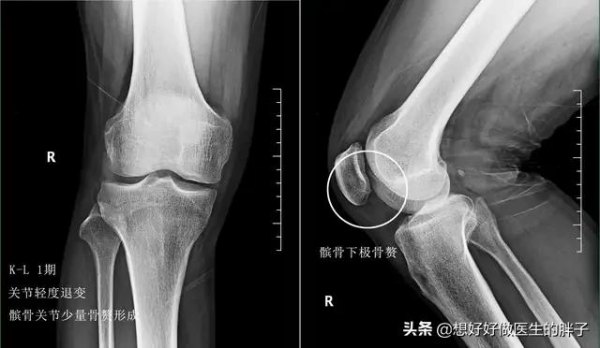

通常情况下,我们根据膝关节x线的表现中关节间隙是否狭窄,以及骨赘形成的程度将骨关节炎分为4期。

一期、二期的骨关节炎,往往关节间隙狭窄的并不明显,可以看到有少量的骨赘形成,患者疼痛的症状也不是特别重。